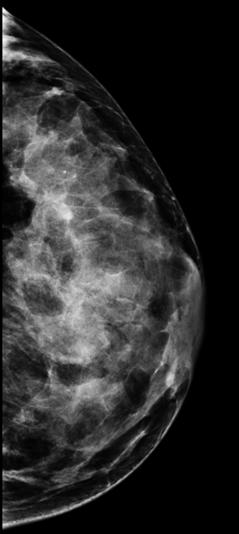

Te hemos hablado de mamografía, pero te preguntarás: ¿qué es? La mamografía es una técnica radiológica especializada que utiliza rayos X para obtener imágenes precisas del tejido mamario. Se emplea principalmente para el tamizaje y diagnóstico del cáncer de mama.

Durante este examen, la paciente se coloca frente a un aparato de rayos X de baja dosis, diseñado especialmente para comprimir las mamas entre dos placas. Esta comprensión ayuda a extender el tejido mamario, lo que garantiza la obtención de una imagen nítida de las estructuras internas de la mama.

En este contexto, la mamografía de tamizaje es una herramienta esencial para la detección temprana en mujeres asintomáticas y el radiólogo es el encargado de su interpretación. Además de esta técnica de imagen, se realizan otros estudios, como ecografías mamarias, resonancias magnéticas y biopsias guiadas por imagen. Estos estudios complementan la información proporcionada por las mamografías, al ofrecer detalles adicionales sobre las características de las lesiones en caso de obtener un resultado positivo.

La densidad mamaria se refiere a la cantidad de tejido glandular* presente en las mamas de una mujer. Cuando un seno tiene una mayor proporción de tejido glandular en comparación con el tejido graso*, se considera que tiene una densidad mamaria alta.

La única forma de conocer si tienes densidad mamaria alta es realizándote una mamografía.